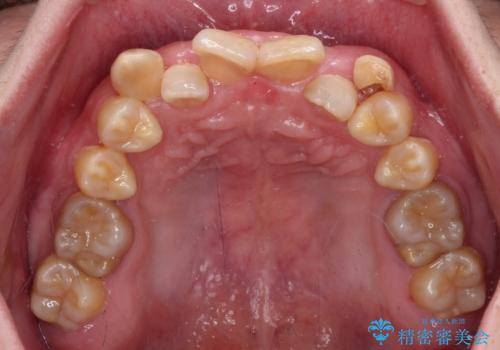

- 上下の前歯のデコボコを改善したいと来院された患者様です。

上顎の歯列幅が狭く、それによって歯が並ぶスペースが不足しています。

また下顎の歯列幅も制限され、内側に歯が倒れています。

それらを改善するため上顎に拡大装置を用いて、審美装置にてワイヤー矯正を行いました。

左上の乳犬歯は当初保存する計画でしたが、虫歯が大きいため抜歯になり、患者様の希望によりブリッジにしました。